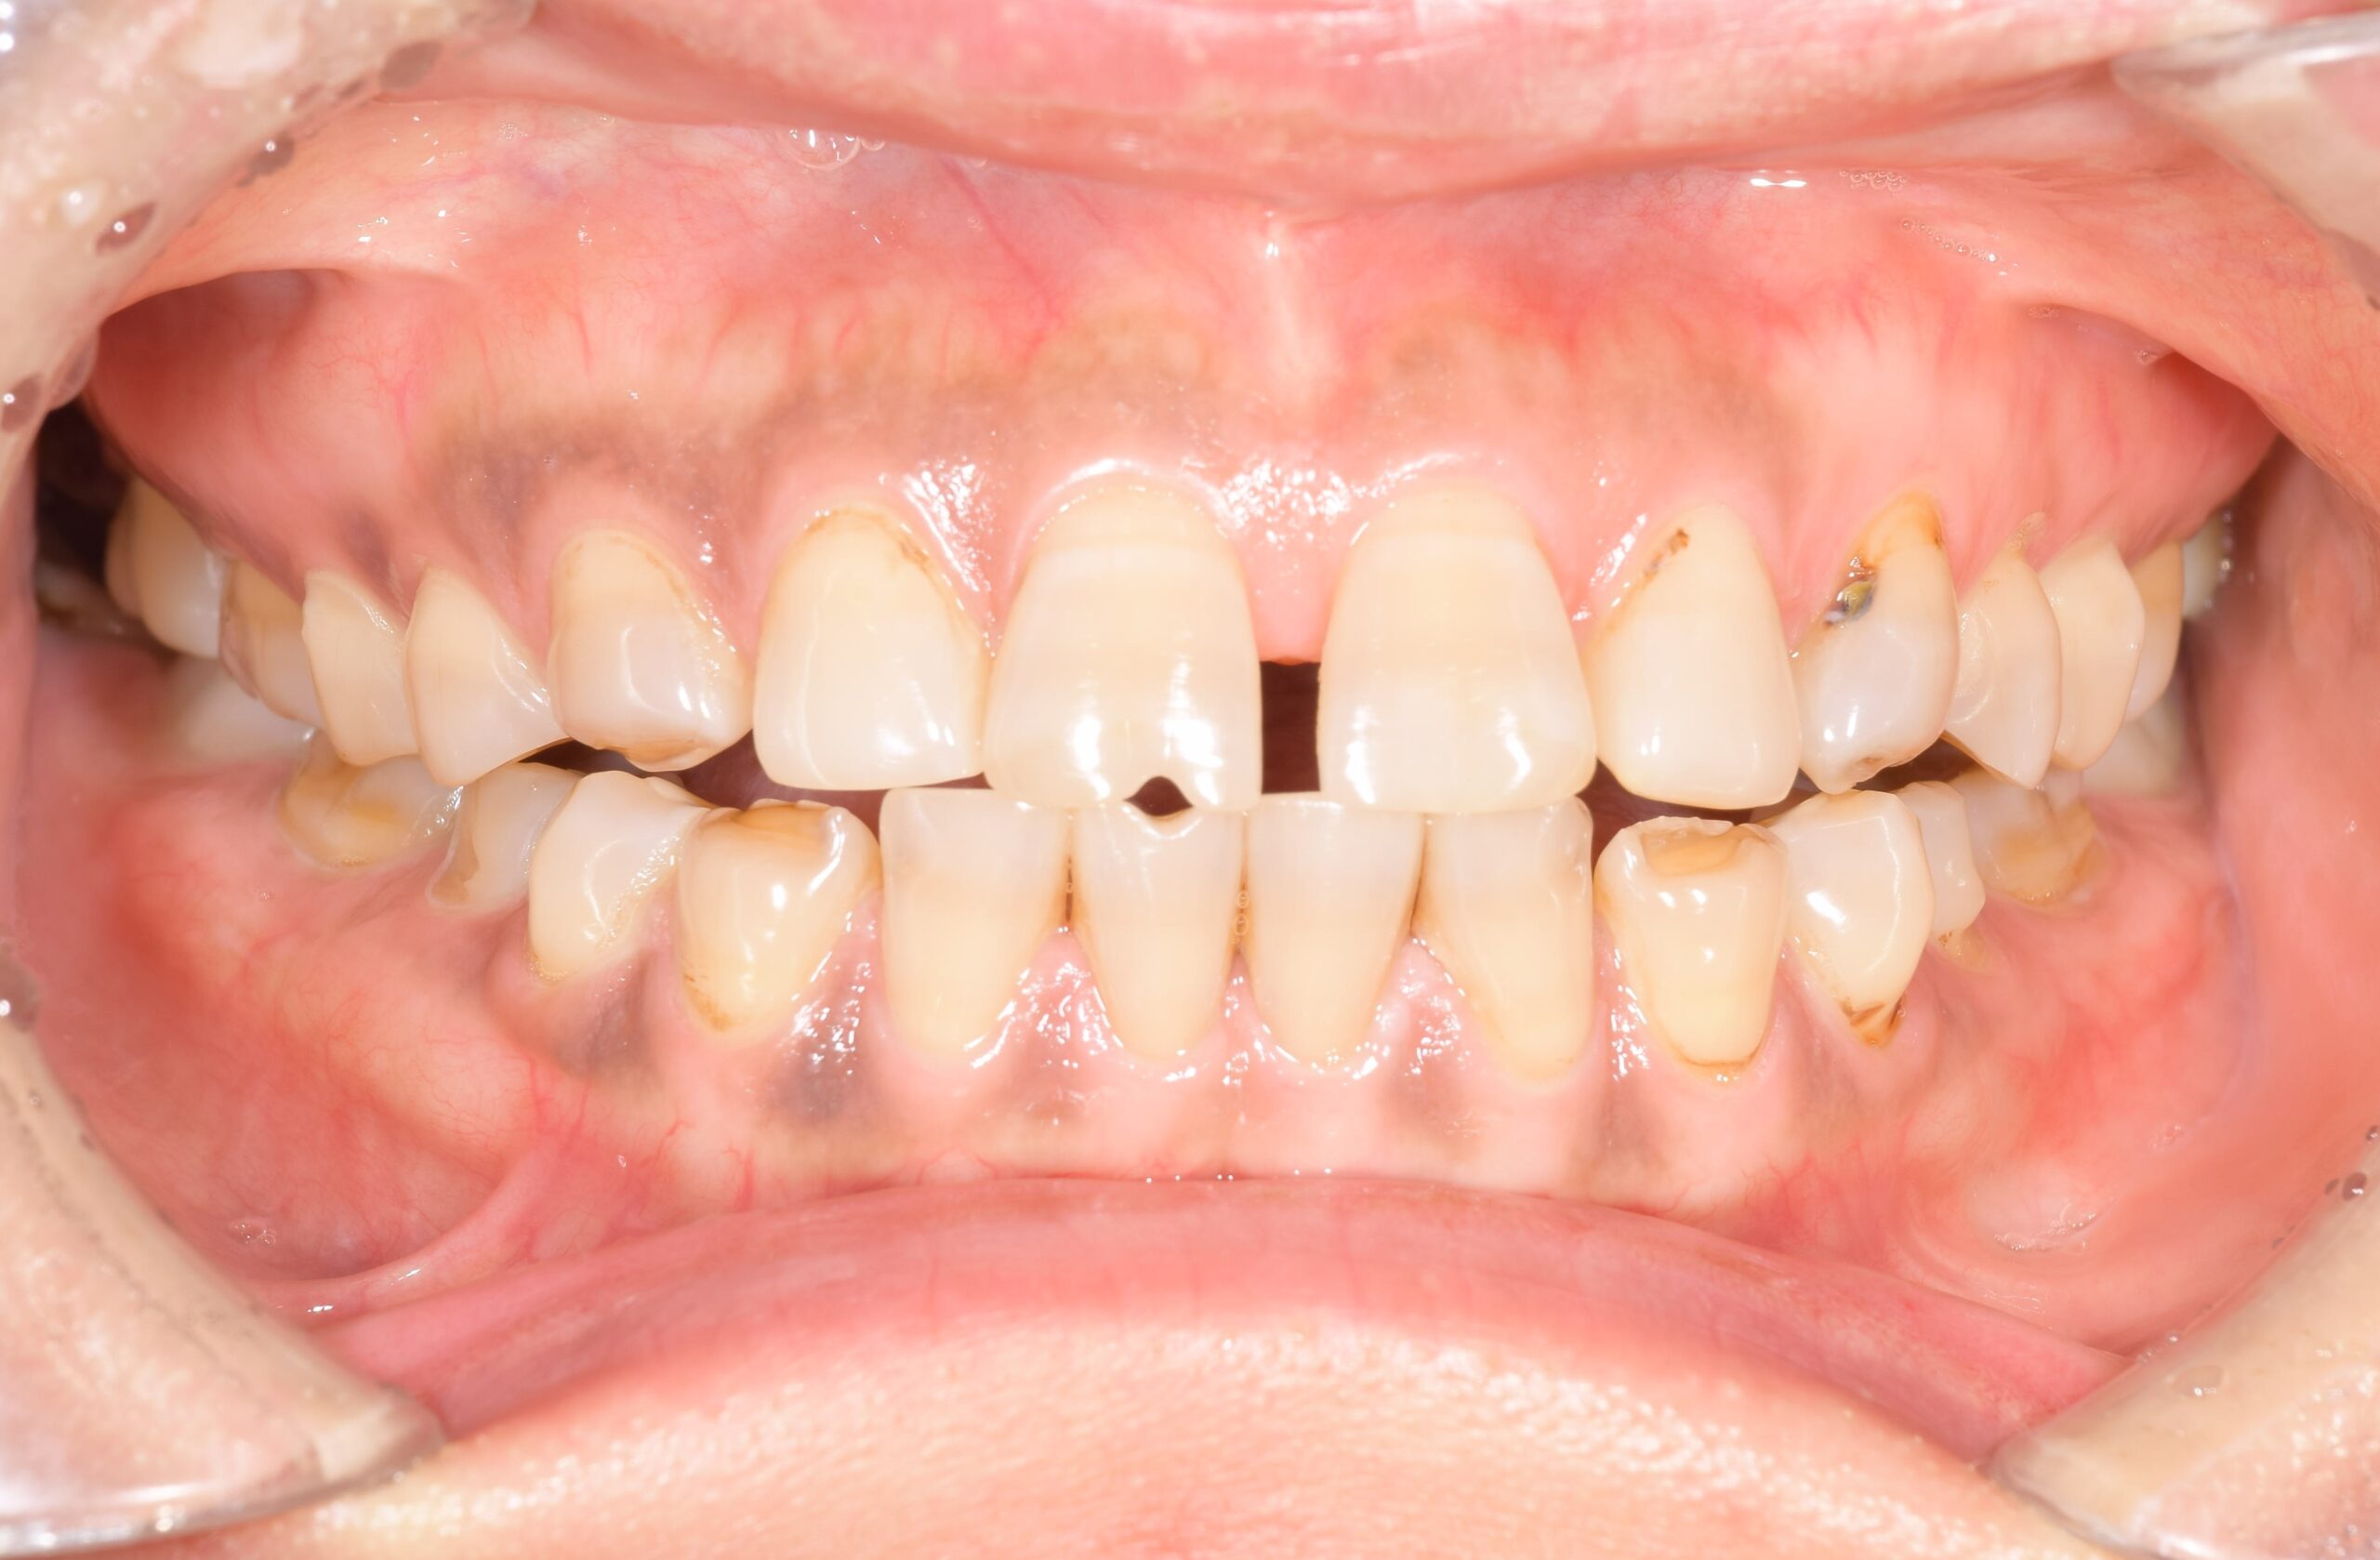

治療概要

| 症状 | 異常咬耗による咬合不全 審美障害 極度の知覚過敏 |

|---|---|

| 年齢 | 38歳 |

| 原因 | 極度の歯ぎしり 顎関節症(非復位性関節円板前方転位) |

| 治療法 | 歯周基本治療 全顎矯正治療にて適正顎位での咬合再構成 その後、全顎歯冠修復 |

| 治療費(目安) | 約500万円(料金改定前) |

治療前-治療後